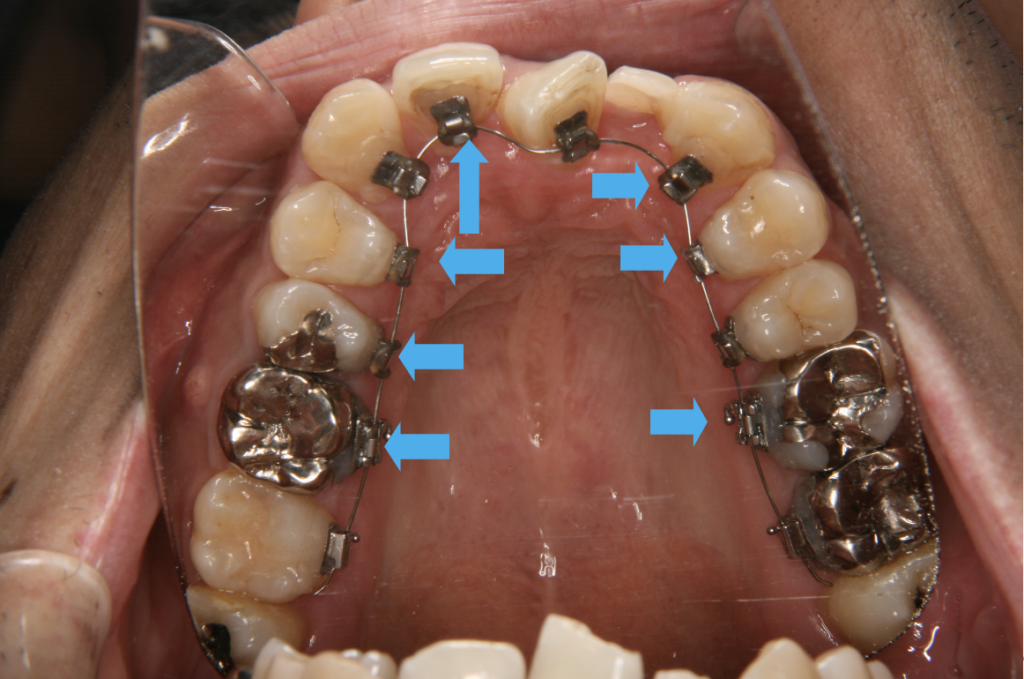

マルチブラケット装置には唇側と舌側がありますが、どちらも食べかすが溜まりやすいのは歯茎と装置の間です。

(図4,5矢印)この部分に付着したプラークはむし歯、歯周病両方の原因になるため優先的にブラッシングによる清掃が必要です。

図5マルチブラケット装置(舌側)